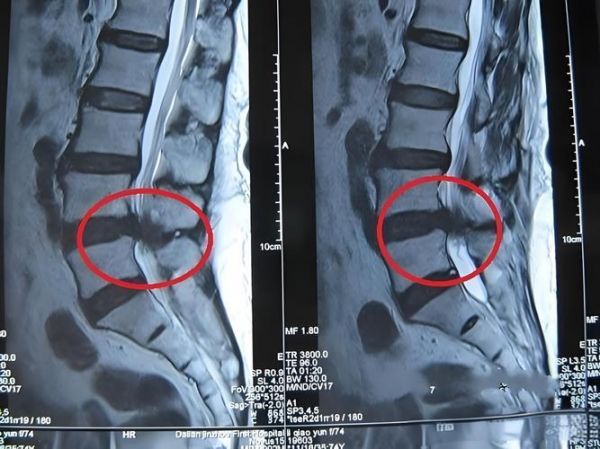

以市民刘先生为例,他右侧臀部及右下肢的疼痛已经持续数月,尽管他尝试休息来缓解,但疼痛却愈发剧烈,最近更是严重到无法行走。他尝试服用止痛药,却无法得到缓解。最终,他只能前往桐乡市第二人民医院寻求帮助。经过医生方敏的详细检查,刘先生被确诊为腰椎间盘突出症,其疼痛源于神经受压。